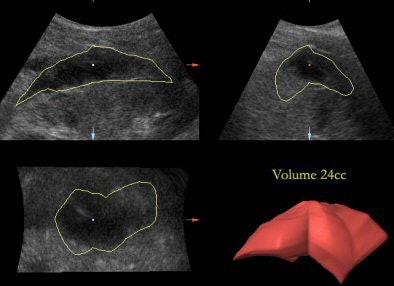

VOCAL is an add-on software application that comes with the package of 3D and 4D ultrasound machines. It can calculate volumes in a more precise manner than the ellipsoidal formula for volumes, which was previously used. VOCAL is precise and easily reproducible, especially with irregular-shaped collections.

| An irregular-shaped perinephric collection showing calculation of volume using the VOCAL software on 3D volume. |